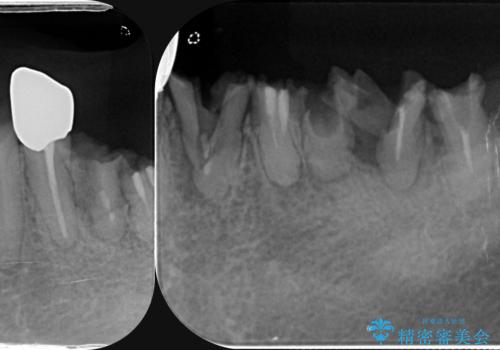

虫歯による歯の喪失 インプラントによる咬合機能回復

- 深い虫歯や歯の破折、多数の問題を口腔内に抱えて来院されました。

虫歯の徹底的な除去、安定した噛み合わせを達成するインプラント治療、深い虫歯、根管治療といった複数の治療項目を一つづつ積み重ね、長期的な予後を目指します。